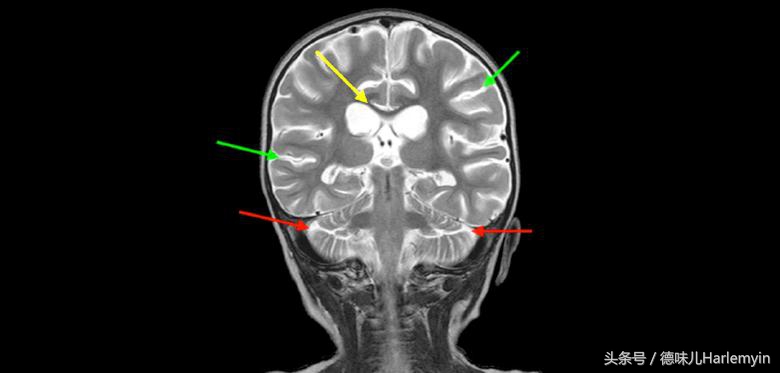

虽然没有彻底脑死亡,但长时间缺氧还是让女孩有重度脑损伤(下图为女孩MRI),她的部分脑组织已经产生永久性损伤,脑神经和脑细胞也出现了大面积退化。医生预测她将来可能无法说话,对外界也不会产生反应。48天的强化治疗后,Eden Carlson出院了,出院时她有不自主的摇头、只能躺在床上、双腿无知觉、对外界也毫无反应。

MRI结果也显示,Eden Carlson脑皮质和神经链已经恢复, 受伤脑组织竟然几乎找不到了,这一结果让医生们吃了一惊,因为这是迄今为止高压氧舱治疗脑损伤最成功的一个案例,病人大脑几乎完全恢复到了脑损伤之前的状态。不过,这并不意味着高压氧舱就包治脑损伤了,因为这只是一个孤例。其他类似病人当然也可以接受这样的治疗,但效果就不一定有这么好了,甚至可能都不会有太大效果。